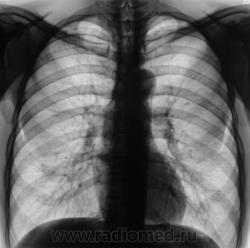

Прошло достаточное количество времени, и сегодня пациент пришел на плановое рентгенологическое исследование. Снимки ниже.

А слева и без врачей не плохо рассосалось.